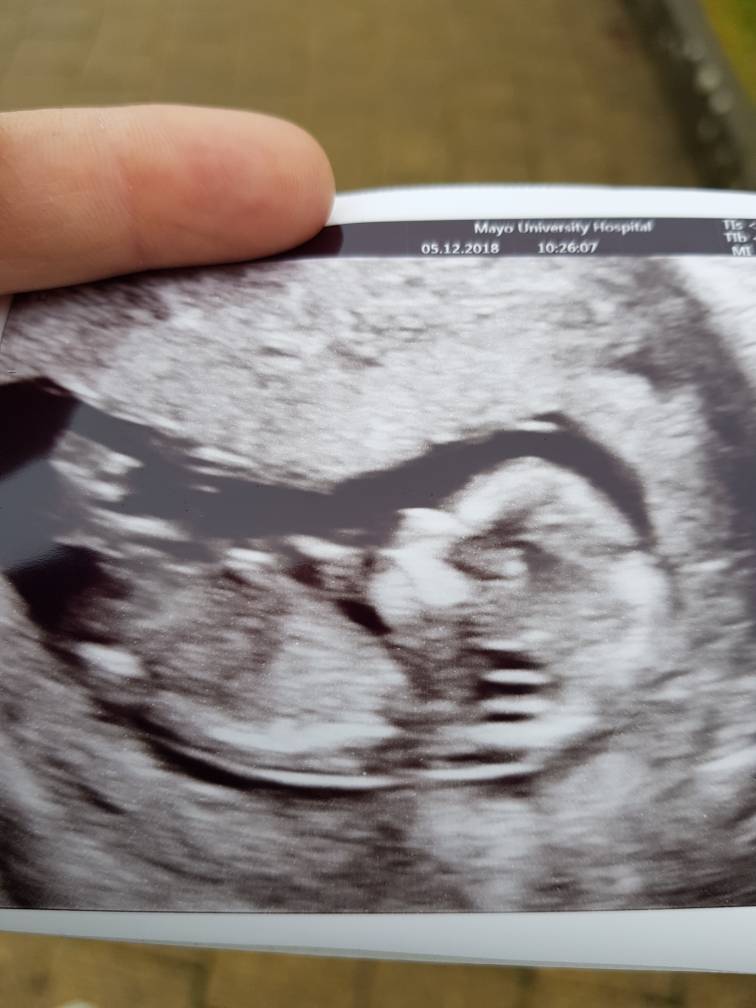

Dzisiaj mieliśmy wszystkie badania. NT 1,5 i kość nosowa obecna. Zrobiłam też dzisiaj test Pappa. Według usg mam 13+5 tc. Dzieciaczek ma 7,5 cm a z nogami 10 cm :)

A tu bobas :) Zobacz załącznik 923552